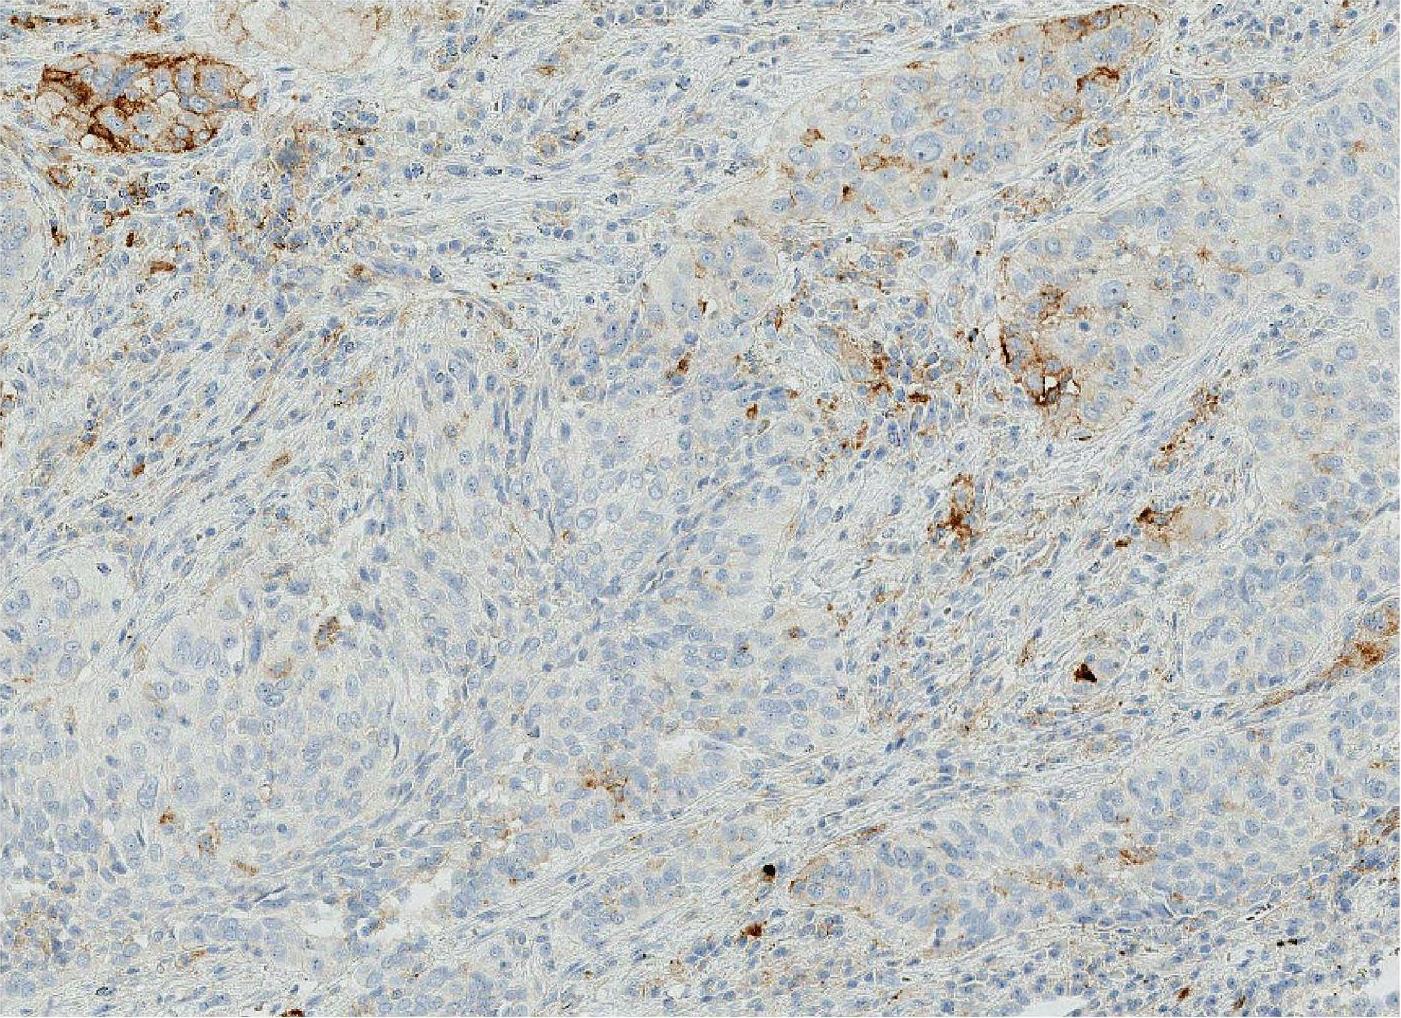

SP142克隆号的操作平台为罗氏诊断Ventana BenchMark Ultra。试剂盒配套完善,只需要灌注好大容量缓冲液及试剂,操作简单,做好质控结果同样稳定可靠,判读结果以TC和IC计算。具体评分时,TC、IC各采用4等级评分。其中TC膜染色4等级:0≤0级<1%、1%≤1级<5%、5%≤2级<50%、3级≥50%;IC染色也同样分为4等级:0≤0级<1%、1%≤1级<5%、5%≤2级<10%、3级≥10%。评分采用逐级评分步骤,先评估TC染色,若TC评分≥50%,则不必再评估IC;若TC评分<50%,则需要进一步评估IC染色。建议检测时TC和IC各自给出评分和(或)级别。TC评分0~3级的NSCLC PD-L1 (SP142)免疫组织化学染色结果分别如图2-18至图2-21所示。

IC评分0~3级的NSCLC PD-L1 (SP142)免疫组织化学染色结果分别如图2-22至图2-25所示。